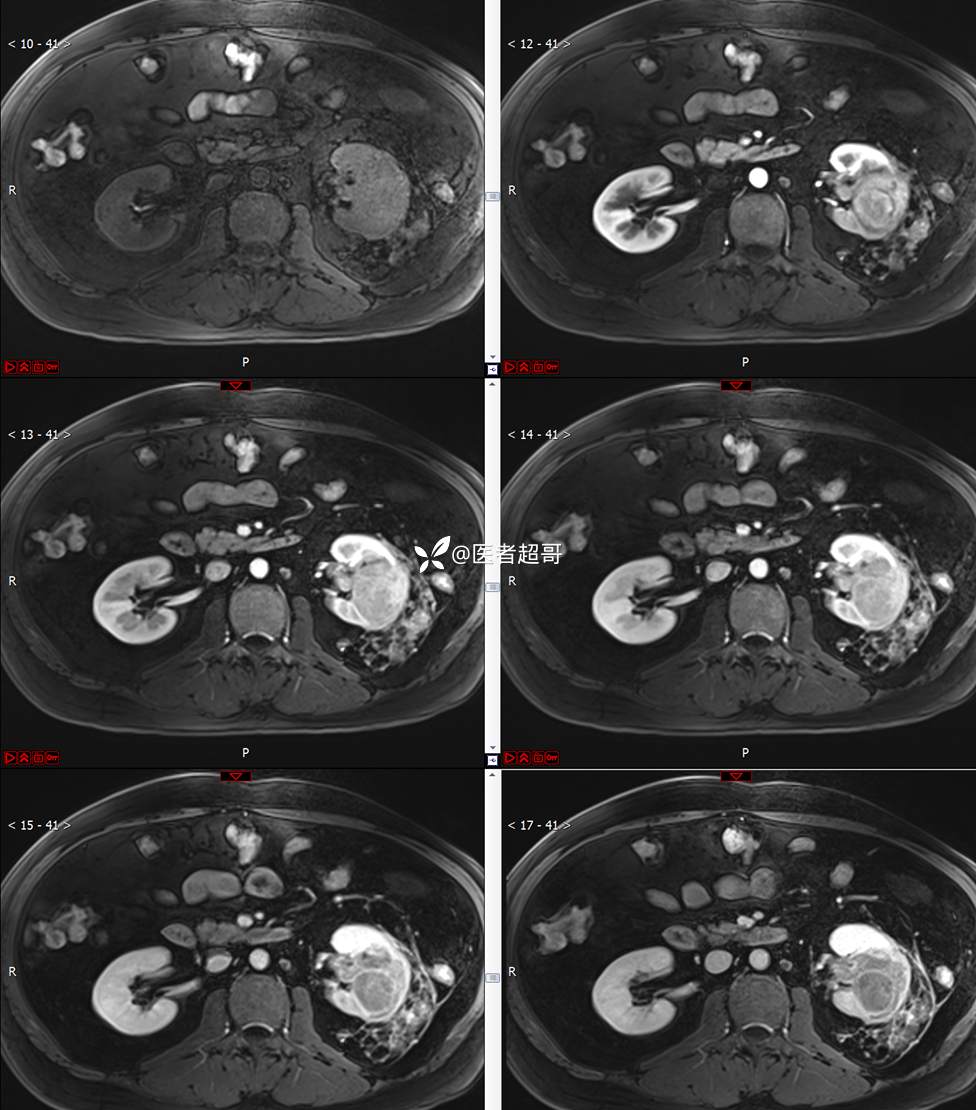

主 诉:查体发现左肾肿物9天。

现病史:患者9天前于附属医院行常规腹部CT检查时,发现左肾占位性病变并肾周脂间隙软组织增多,自述无明显腰腹部不适,无尿频、尿急、尿痛及肉眼血尿,未予特殊治疗,患者近期无头晕头迷,胸闷气急,腹胀腹泻及其他部位明显不适,遂至我院就诊,门诊以“肾肿物”收入院,患者自发病以来,精神可,睡眠饮食可,大便正常,体重无明显减轻。